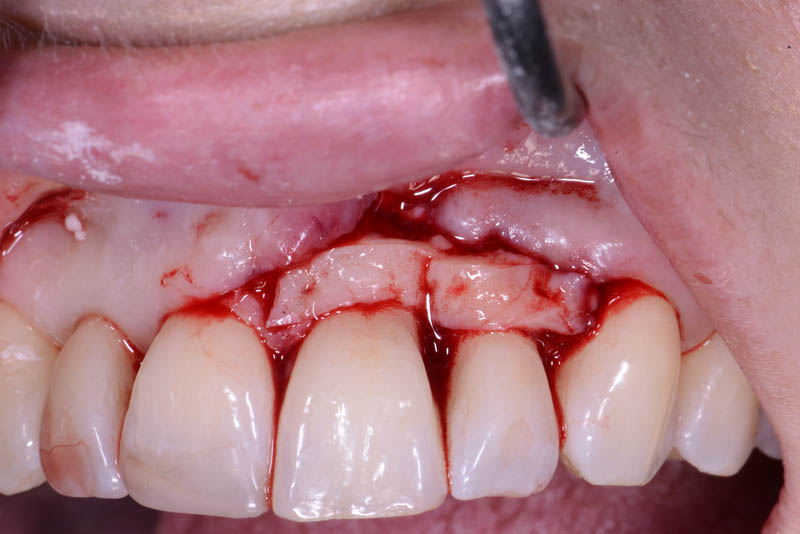

At the end of the orthodontic treatment, a coronally advanced flap was performed according to the De Sanctis and Zucchelli technique, involving papilla preservation and connective tissue grafting, to restore the gingival contour and the papilla between teeth 21 and 22.